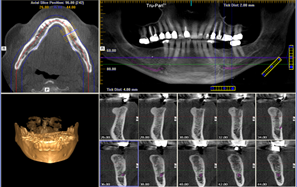

显示种植体和上颌窦植骨移位

根尖周炎:冷热试验; CBCT、口腔全景片PAR 或 根尖拍片OP

7、牙科常见的检查包括:CBCT(相比普通鼻窦CT能更好的显示牙齿问题,下图);口腔全景片,根尖X拍照,牙髓温度测试